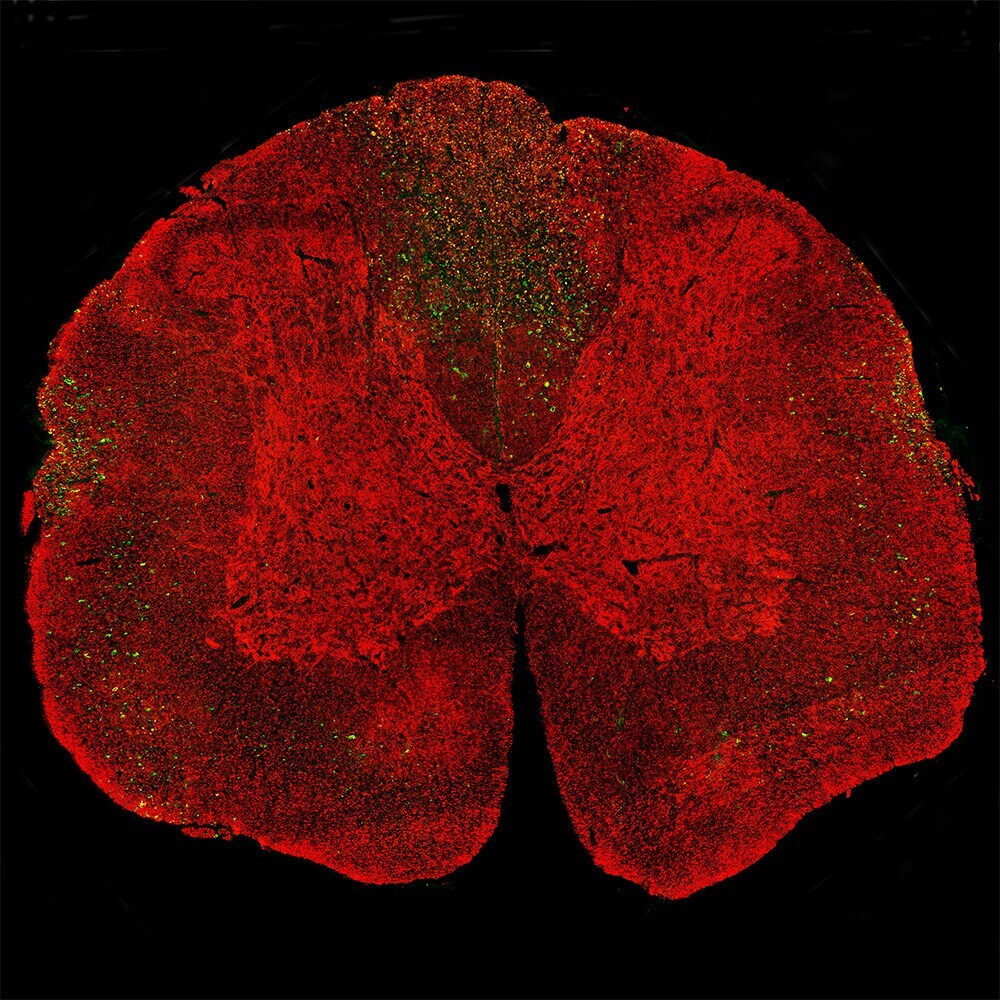

- Immunohistochemistry analysis of NEFL in coronal section of the spinal cord of a rat given a midline C4 contusion injury three days previously. Samples were stained with NEFL monoclonal antibody (Product # MA5-47382) in green. Costained with rabbit polyclonal antibody to neurofilament NF-L C-terminus in red. The NEFL antibody stains prominent aggregates of material concentrated in the lateral funiculi and the dorsal columns but seen in lesser amounts throughout the section. These are degenerating and degenerated axons damaged by the C4 lesion. The neurofilament NF-L C-terminus antibody binds the C-terminal "tail" region of NF-L which is absent or destroyed during degeneration, so the NEFL positive profiles are largely negative for neurofilament NF-L C-terminus antibody.